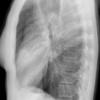

Case 4 RML pneum Lat

Date: 04/16/2005

Views: 5342